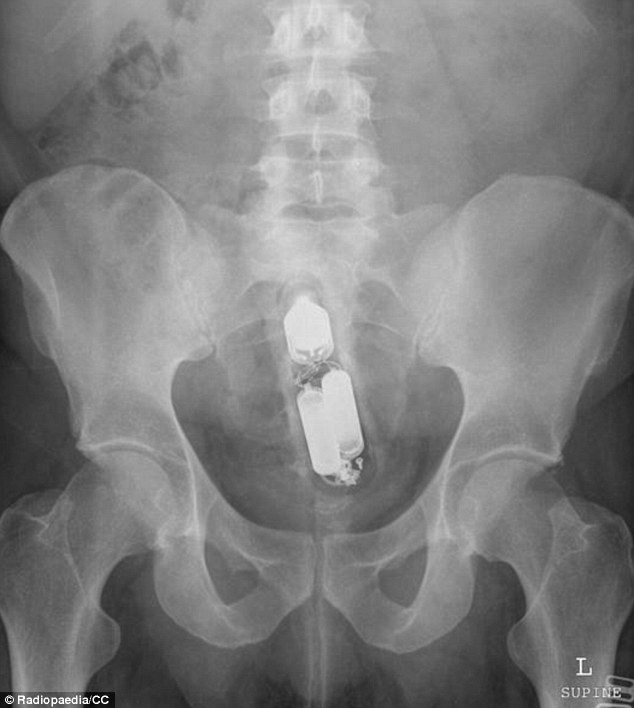

| Bác sĩ rất ngạc nhiên khi thấy chai khử mùi mắc kẹt trong trực tràng. Các nhân viên y tế chia sẻ hình ảnh X-quang những dị vật lạ lùng trên Radiopaedia - trang web chia sẻ tài liệu dành cho chuyên viên X-quang. |